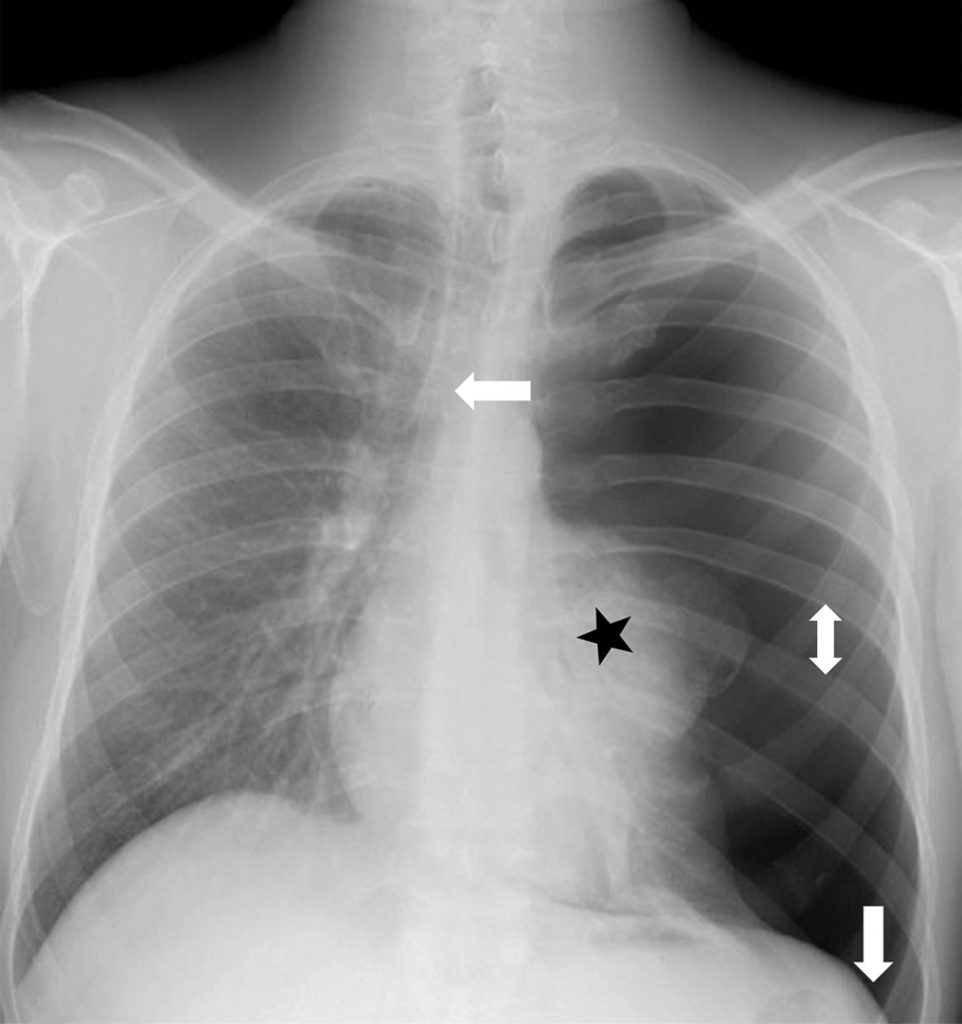

La radiographie thoracique montre que le bord externe de la plèvre pulmonaire, sous la forme d’une fine ligne qui croise l’arc postérieur des côtes, est séparé de la paroi par un croissant gazeux clair avasculaire (figures 98.1 et 98.2). Les signes de pneumothorax sous-tension (figure 98.3) sont un déplacement médiastinal vers le côté opposé, un aplatissement de la coupole diaphragmatique homolatérale, une expansion de la cage thoracique et un poumon dense collabé au hile.

Fig. 98.3. Radiographie de face. Pneumothorax gauche sous tension.

Le poumon gauche est entièrement collabé au hile (étoile). Les signes d’expansion de la cage thoracique sont une déviation du médiastin du côté opposé (flèche blanche vers à droite), un refoulement vers le bas de la coupole diaphragmatique gauche (flèche blanche, vers le bas) et un élargissement des espaces intercostaux (par exemple, celui indiqué par la double flèche blanche verticale).

Source : CERF, CNEBMN, 2022.